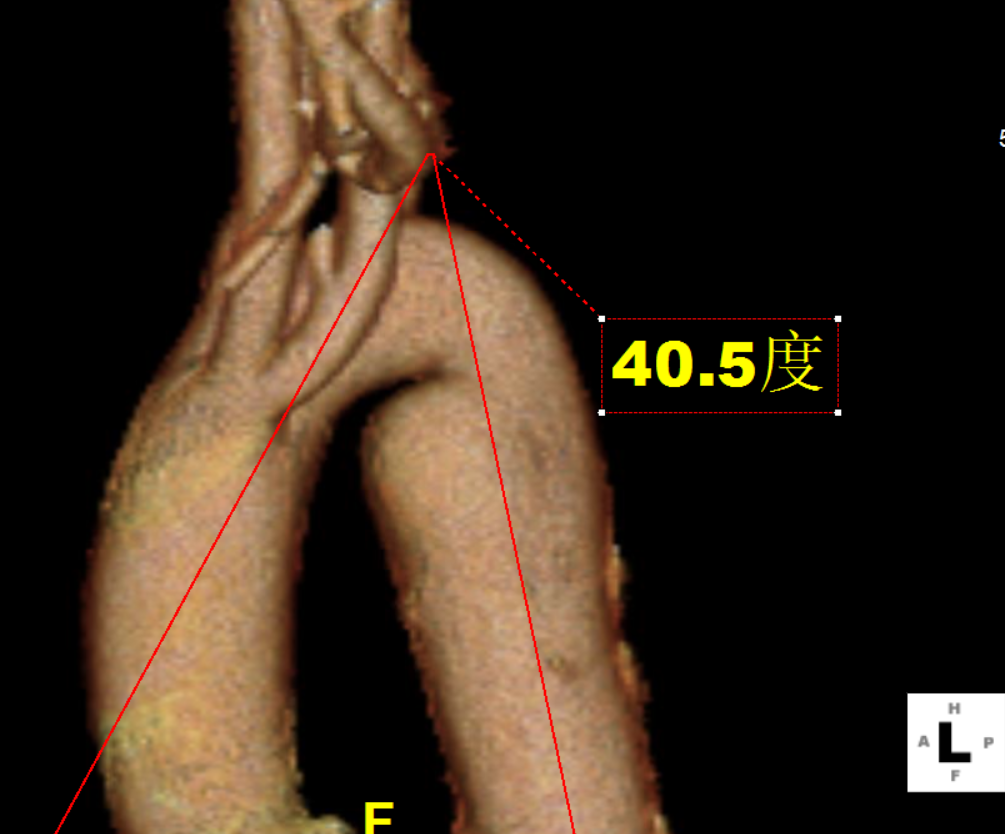

术前CTA提示右弓右降、合并Kommerell憩室,弓上各分支镜像分布。测量如下:

右弓右降,弓型陡峭,角度在40°左右

Kommerell憩室,38mm*30mm